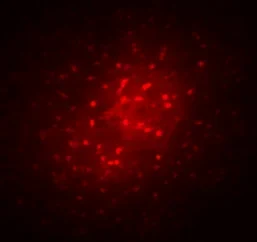

Das Bild entstand,

Das Bild entstand, - indem in einem Hirnschnitt ein Astrozyt mit einem Marker (Biozytin, rot) gefüllt wurde. Dieses Molekül diffundiert bei intakter Kopplung in benachbarte Astrozyten, so dass ein ganzes funktionelles Netzwerk sichtbar wird. © Foto: Institut für Zelluläre Neurowissenschaften/Uni Bonn

Im Gewebe von Patienten mit Schläfenlappen-Epilepsie

Im Gewebe von Patienten mit Schläfenlappen-Epilepsie - verbleibt das Biozytin in der initial gefüllten Zelle. Eine Ausbreitung in Nachbar-Zellen ist nicht möglich, da die Zellen entkoppelt sind. © Foto: Institut für Zelluläre Neurowissenschaften/Uni Bonn